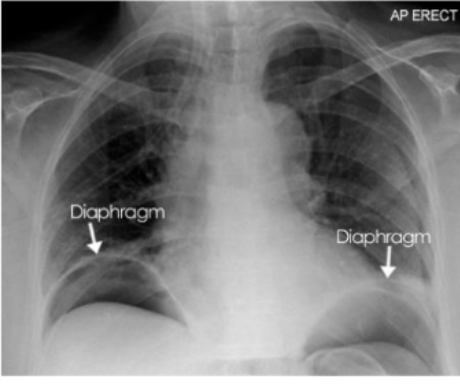

What is this and what type of scan

free gas under the diaphragm 2/2 perforated duodenal ulcer (abnormal bowel gas pattern), ABX